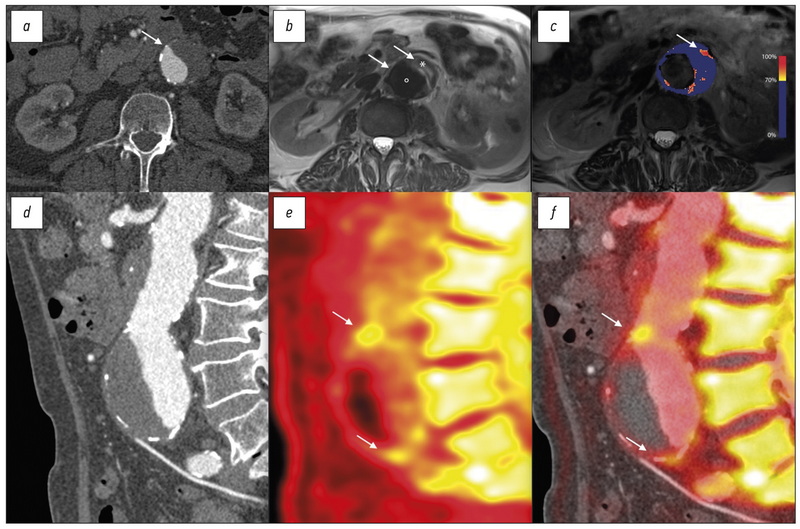

Объективные критерии МРТ-оценки эффективности лечения метастазов в кости у больных раком предстательной железы и раком молочной железы: систематический обзор и метаанализ

Аннотация

Обоснование. Возможность персонифицированного подхода к лечению метастатического рака предстательной железы (РПЖ) и рака молочной железы (РМЖ) требует объективных методов оценки ответа на лечение очагов в скелете. Доказанная высокая эффективность МРТ в выявлении метастазов в кости в сочетании с отсутствием ионизирующего излучения создаёт предпосылки для использования метода в мониторировании хода лечения на основе объективных критериев оценки терапевтического эффекта.

Цель ― оценить возможности объективных количественных и полуколичественных МРТ-критериев в определении эффективности лечения (радио-, химио-, гормоно- и таргетная терапия) метастазов в кости, применявшихся в клинических исследованиях у больных РПЖ и РМЖ.

Материалы и методы. Поиск в базах данных Embase, PubMed, Cochrane Central Register of Controlled trials (CENTRAL), eLibrary осуществлялся до 01.06.2021 по ключевым словам «magnetic resonance imaging», «MRI», «DWI», «treatment response», «prostate cancer», «breast cancer», «bone metastasis» на английском и русском языках. В обзор включали только исследования по объективной МРТ-оценке эффективности любого типа лечебного воздействия (за исключением хирургии) при метастатическом поражении скелета.

Результаты. На основании анализа 11 исследований, отобранных из 312 источников, выделены 4 группы объективных МРТ-критериев оценки терапевтического эффекта при метастатическом поражении костей у больных РПЖ и РМЖ, включающих динамику размеров, интенсивности сигнала на диффузионно-взвешенном изображении, числовых значений измеряемого коэффициента диффузии (ИКД), общей опухолевой нагрузки. Изменения этих количественных и полуколичественных показателей во всех работах, за единственным исключением, имели одинаковую направленность, хотя и различались числовыми значениями. Учитывая статистически значимую гетерогенность (p <0,1 для критерия χ2 и при I2 >40%) для значений ИКД до и после лечения, для анализа использовалась модель случайных эффектов. Изменение ИКД в результате лечения в среднем составило +0,35 [+0,12; +0,49] ×10-3 мм2/с со средними значениями ИКД до лечения 0,83 [0,71; 1,03] ×10-3 мм2/с, после лечения ― 1,18 [0,83; 1,49] ×10-3 мм2/с.

Заключение. МРТ является информативной методикой для объективной оценки ответа костных метастазов на терапию у больных РПЖ и РМЖ на основе количественных и полуколичественных критериев и имеет значительный потенциал в качестве диагностического инструмента для мониторирования эффективности лечения метастатического поражения скелета.

289-300